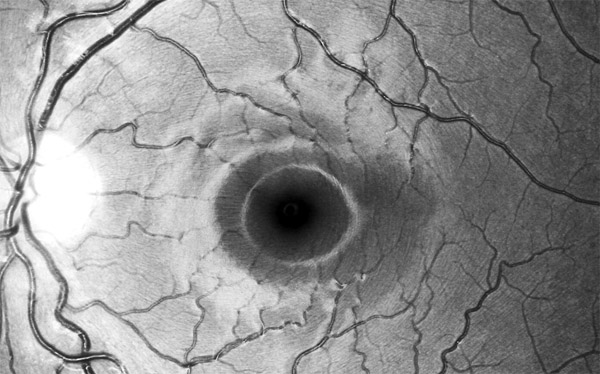

Vrstva nervových vláken

Oftalmo-neurologická diagnostika 1956, Michelem popsaný obraz si můžeme kdykoliv vyvolat, vyšetřujeme-li oční pozadí podle Vogtova návrhu bezčerveným světlem.

The temporal raphe of the human retina Amer.J.ophthal. 62:926/1966, popsal předěl ve vrstvě nervových vláken temporálně od makuly mezi horní a dolní polovinou sítnice.